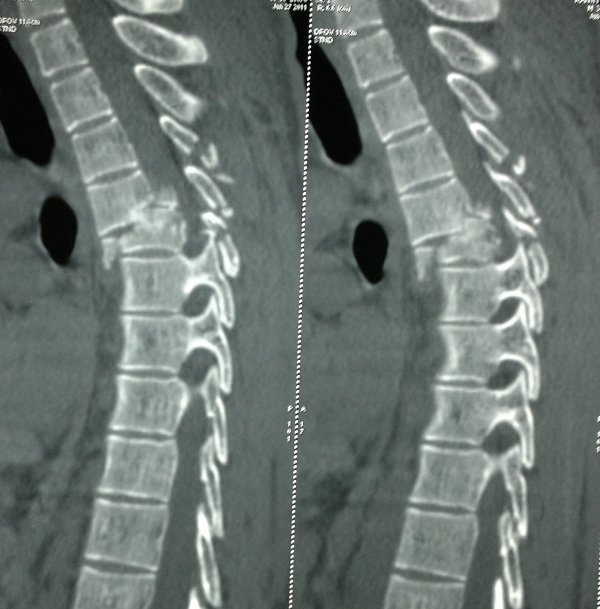

SPINAL FRACTURES AND DISLOCATIONS

The most common cause of spinal fractures and dislocations in India is road traffic accidents followed by fall from height (usually a fall from tree). Spinal fractures can damage the spinal cord, resulting in paralysis. This paralysis can be permanent, and have devastating consequences on the patient and his family.

Some of these patients may need a Spine Surgery to fix these fractures. This may be done using plates or rods and screws made of Titanium. Some of these fractures can be fixed using Minimally Invasive Spine Surgery (MISS).

Patients with paralysis almost always require a Spine Surgery to decompress the spinal cord and to fix their neck or back. If the paralysis is incomplete to start with, one can hope for the paralysis to improve over a period of 3 months to 1 year.

If the paralysis is complete at the time of injury it may never recover. The aim of surgery in patients with complete paralysis, is to facilitate their nursing care; prevent bed sores and pneumonia; and mobilize them at the earliest on a wheel chair. Unfortunately, ongoing research from all over the world is yet to find an effective treatment by which patients with complete paralysis can be made to walk again.